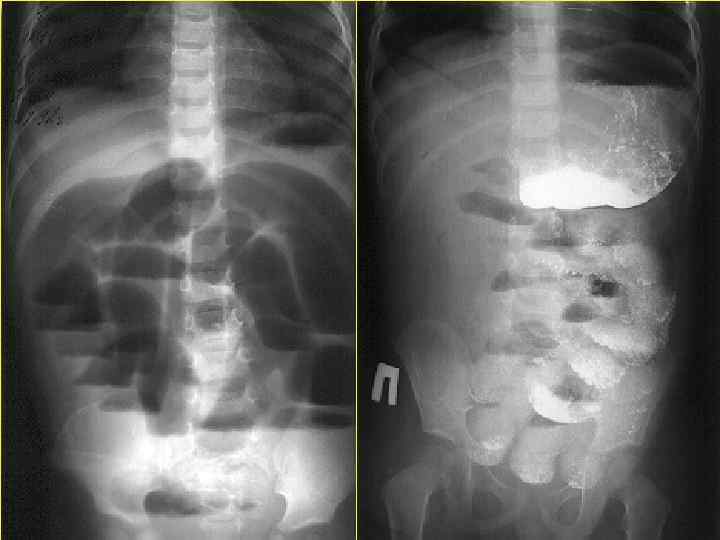

АНОМАЛИИ РАЗВИТИЯ ОРГАНОВ ПИЩЕВАРЕНИЯ